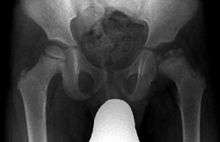

| X ray of Legg–Calvé–Perthes disease of the right hip (left side of X-ray) | |

Legg–Calvé–Perthes disease (LCPD) is a childhood hip disorder initiated by a disruption of blood flow to the ball of the femur called the femoral head. Due to the lack of blood flow, the bone dies (osteonecrosis or avascular necrosis) and stops growing. Over time, healing occurs by new blood vessels infiltrating the dead bone and removing the necrotic bone which leads to a loss of bone mass and a weakening of the femoral head.[1] The bone loss leads to some degree of collapse and deformity of the femoral head and sometimes secondary changes to the shape of the hip socket. It is also referred to as idiopathic avascular osteonecrosis of the capital femoral epiphysis of the femoral head since the cause of the interruption of the blood supply of the head of the femur in the hip joint is unknown.

X-rays of the hip may suggest and/or verify the diagnosis. X-rays usually demonstrate a flattened, and later fragmented, femoral head. A bone scan or MRI may be useful in making the diagnosis in those cases where X-rays are inconclusive. Usually, plain radiographic changes are delayed 6 weeks or more from clinical onset, so bone scintigraphy and MRI are done for early diagnosis. MRI results are more accurate, i.e. 97 to 99% against 88 to 93% in plain radiography. If MRI or bone scans are necessary, a positive diagnosis relies upon patchy areas of vascularity to the capital femoral epiphysis (the developing femoral head).